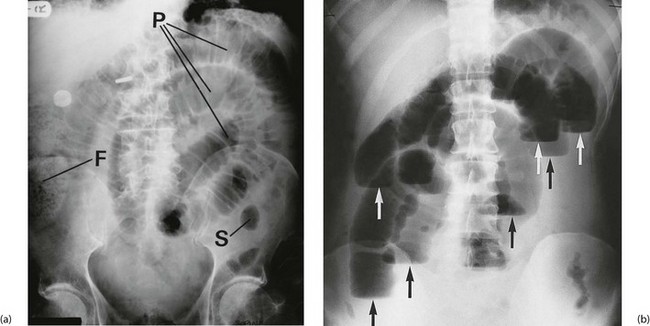

Fig. 19.2 Radiological appearances of obstructed bowel

(a) Supine abdominal film in a man of 67 presenting with vomiting and abdominal distension. The film shows mid small bowel obstruction. Dilated small bowel fills the upper left quadrant and centre of the abdomen, and can be identified by the valvulae conniventes (plicae circulares P) which extend across the whole width of the lumen. The small bowel distal to the obstruction is collapsed and is not visible on this film. The large bowel is also collapsed, with faecal loading of the ascending colon (F) and only a small amount of gas in the sigmoid colon (S). Note also the metallic tip of the nasogastric (NG) tube and the incidental radiopaque gallstone.

(b) Erect film showing multiple loops of dilated small bowel and multiple fluid levels. The obstruction was caused by a small carcinoma of the medial wall of the caecum encroaching upon the ileal opening. Note: erect abdominal films are rarely taken nowadays